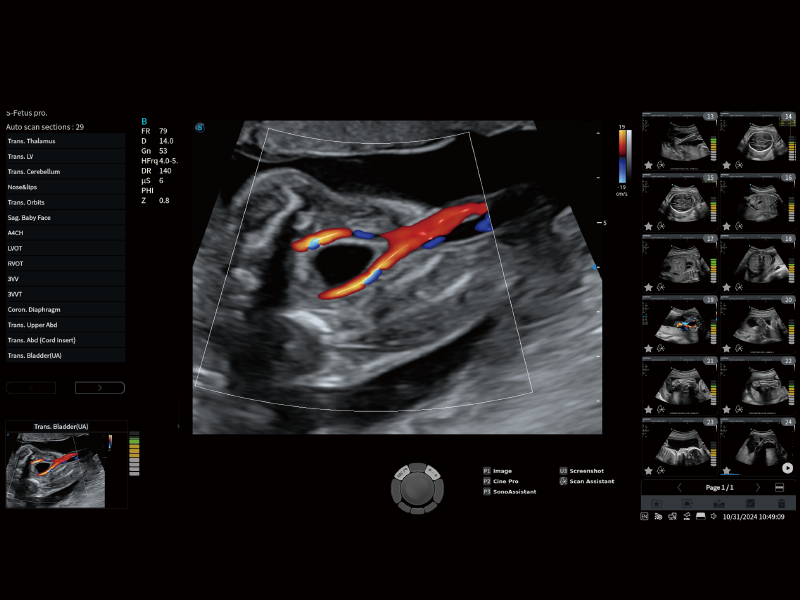

扫查助手

根据预设流程可自动添加注释、体标及自动激活测量等,同时结合教学系统,帮助操作者顺利完成检查工作

提供解剖示意图、标准超声图像、扫查手法图和操作者实时检查图像,指导操作者进行标准切面的正确扫查。